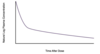

Which letter corresponds with the region where dead space is the greatest?

A

B

C

D

D

Dead space is ventilation without perfusion and shunt is perfusion without ventilation.

The graph examines the V/Q relationship in the entire lung.

Point C marks where ventilation and perfusion are equally matched.

Point D marks the region where ventilation is greater than perfusion; dead space is increased here.

Points A and B mark where perfusion exceeds ventilation; shunt is increased here.